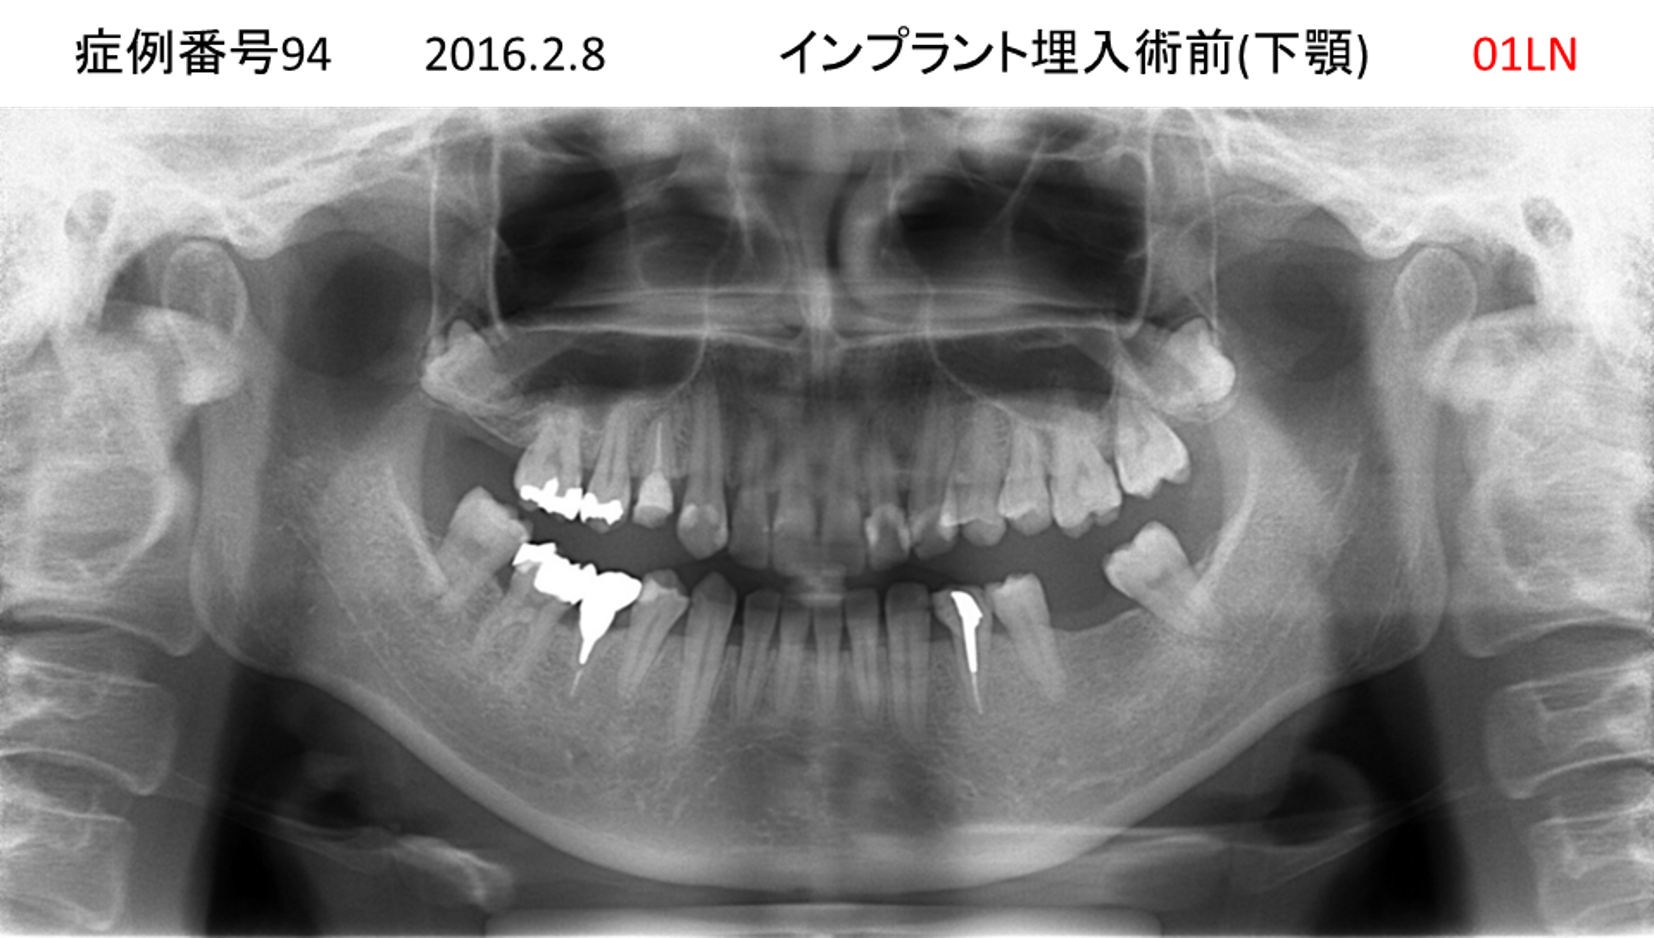

左下の奥歯が痛い患者様のインプラント症例

| 治療名称 |

インプラント |

| 治療費用 |

215万円+税 |

| 治療期間 |

5か月 |

| 患者さんの症状(主訴) |

左下の奥歯が痛い。 |

| 治療内容 |

| 治療結果 |

痛み無く、噛める。 |

| 治療の注意点(リスク/副作用) |

インプラントが壊れたら再治療が必要 |